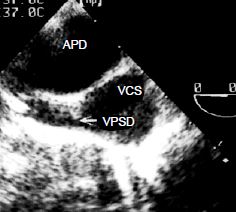

Une ou plusieurs veines pulmonaires, en général droites, peuvent avoir un trajet aberrant vers l'OD au lieu de s'aboucher normalement dans l'OG. Il s'agit le plus souvent d'une veine pulmonaire supérieure droite qui se connecte à la racine de la VCS dans l'OD (Figure 14.34); cette anomalie est fréquemment associée à une CIA de type sinus venosus (voir Figure 15.11C).

Figure 14.34 : Retour veineux pulmonaire anormal partiel. La veine pulmonaire supérieure droite (VPSD) se jette dans la veine cave supérieure (VCS) juste au dessus de son abouchement dans l’OD. APD: artère pulmonaire droite (vue court-axe de l’aorte ascendante 0° avec rotation horaire de la sonde).